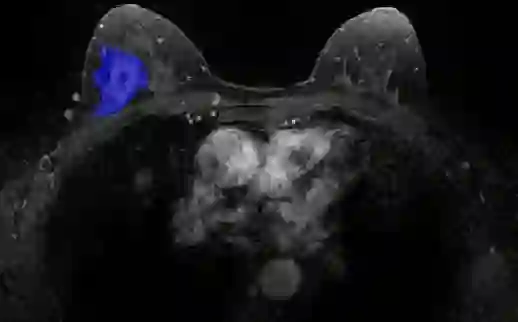

Most papers caution against using predictive models for disease stratification based on unselected radiomic features, as these features are affected by contouring variability. Instead, they advocate for the use of the Intraclass Correlation Coefficient (ICC) as a measure of stability for feature selection. However, the direct effect of segmentation variability on the predictive models is rarely studied. This study investigates the impact of segmentation variability on feature stability and predictive performance in radiomics-based prediction of Triple-Negative Breast Cancer (TNBC) subtype using Magnetic Resonance Imaging. A total of 244 images from the Duke dataset were used, with segmentation variability introduced through modifications of manual segmentations. For each mask, explainable radiomic features were selected using the Shapley Additive exPlanations method and used to train logistic regression models. Feature stability across segmentations was assessed via ICC, Pearson's correlation, and reliability scores quantifying the relationship between feature stability and segmentation variability. Results indicate that segmentation accuracy does not significantly impact predictive performance. While incorporating peritumoral information may reduce feature reproducibility, it does not diminish feature predictive capability. Moreover, feature selection in predictive models is not inherently tied to feature stability with respect to segmentation, suggesting that an overreliance on ICC or reliability scores for feature selection might exclude valuable predictive features.